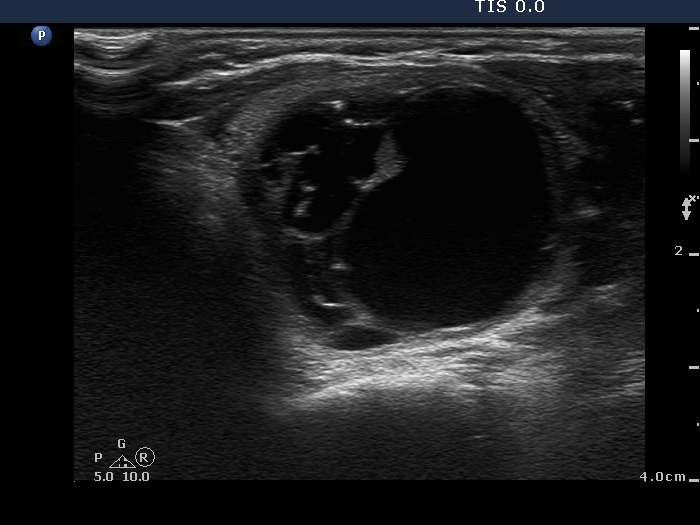

Benign cystic degeneration (cytological diagnosis) - case 662

The bright figures marked with arrows at the border of the cystic and solid part (right side of the nodule in the right image) can be easily misinterpreted as punctate echogenic foci (microcalcifications); these are posterior back wall enhancements caused by the microcystic area ventral to them.

There are comet-tail artifacts within the cystic fluid with a broader than usual tail.